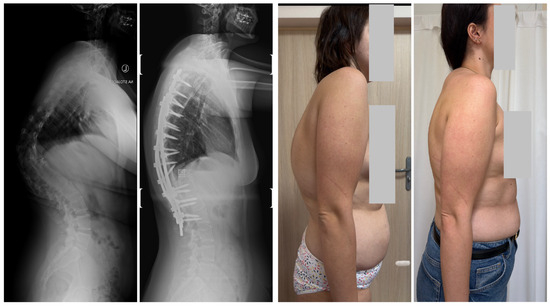

- Grabala, P.; Fani, N.; Gregorczyk, J.; Grabala, M. Posterior-only T11 vertebral column resection for pediatric congenital kyphosis surgical correction. Medicina 2024, 60, 897. [Google Scholar] [CrossRef] [PubMed]